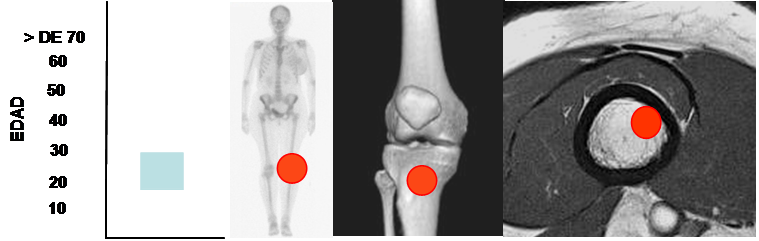

Es frecuente entre los 20 y 30 años. (18). (Fig 106).

Fig 106. Fibroma condromixoide.

Mayor frecuencia entre los 20 y 30 años. Predominio alrededor de la rodilla.

Lesión metafisiaria, de ubicación excéntrica.